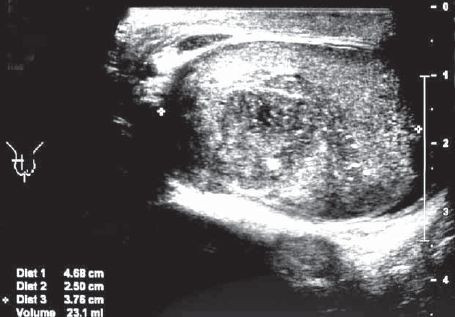

Gynaecomastie bij pasgeborenen, pubers en mannen ouder dan 50 is vaak fysiologisch. Men kan meestal volstaan met geruststelling en afwachtend beleid. Bij patiënten uit andere leeftijdsgroepen kan gynaecomastie, vooral als die in korte tijd ontstaat, een onderliggende oorzaak hebben. …